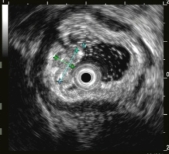

大型超声内镜下(EUS)胰腺占位性病变的FNA/FNB技术

内镜超声小探头行胃、肠道粘膜下隆起病变诊断

胃内粘膜下隆起,术前结合我科超声内镜,诊断考虑异位胰腺。

胃内粘膜下隆起,术前超声提示来源于固有肌层,术前判断需胃壁全层切除。

术中所见与术前判断相符,行内镜全层切除术EFTR,术后严密封闭创面,患者2日后安全出院,术后病理诊断胃间质瘤。